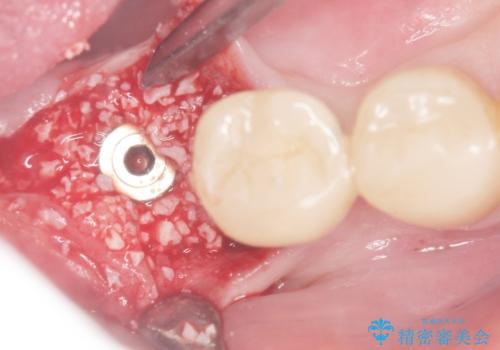

診査の結果、歯根が破折しており保存不可能だったため抜歯し、ブリッジによる補綴を行いました。

今回用いたオールセラミッククラウンはジルコニアフレームという白い素材の上にセラミックを盛っているため、審美性が非常に高いのが特徴です。

また、ジルコニアは人工ダイヤモンドの材料にも使われているほど高い強度を持っており、そのためオールセラミッククラウンは審美性だけでなく、奥歯やブリッジの補綴も可能とするクラウンです。